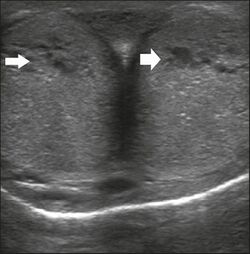

The corpora cavernosa are homogeneous and relatively hypoechoic cylindrical structures lined with tunica albuginea, a thin membrane that has a thickness of approximately 2 mm when the penis is flaccid and 0.25 mm when it is erect. The corpus spongiosum, a ventral, medial body that is more echoic than the corpora cavernosa, is also covered by the tunica albuginea and contains the urethra. As can be seen in Figures 1 and 2, it is more dilated and prominent in its proximal segment, known as the bulb, and in its distal segment, constituting the glans. Buck's fascia is superficial to the tunica albuginea and covers all of the structures described.[1]

Peyronie's disease is characterized by fibrotic thickening of the tunica albuginea, which can lead to curvature of the penis and difficulty in achieving an erection. Penile fibromatosis (Peyronie's disease) is marked by the formation of fibrous plaques identified as areas where the tunica albuginea is thickened. Although plaques are more common on the dorsum of the penis, they can also be seen on the ventral face, lateral face, or septum.[1]